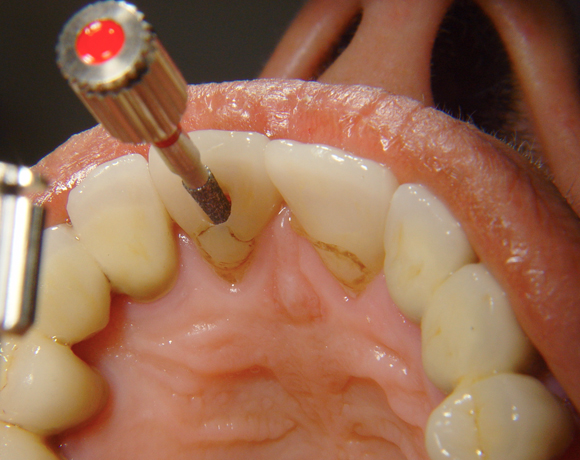

Bei diesem Patientenfall musste nach Neuüberkronung der Frontzähne eine Wurzelbehandlung erfolgen. Um der Gefahr aus dem Weg zu gehen, dass die neue Krone abbricht, da sehr wenig eigene Zahnrestsubstanz nach der endodontischen Behandlung übriggeblieben war, wurde der Zahn nachträglich mit einem Dentinpost versorgt.